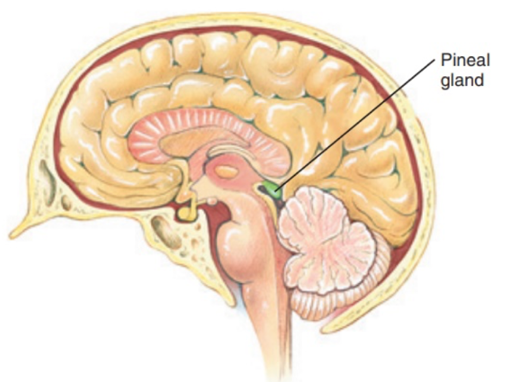

Name this gland

The pinneal gland- part of the epithalamus, posterior to the thalamus